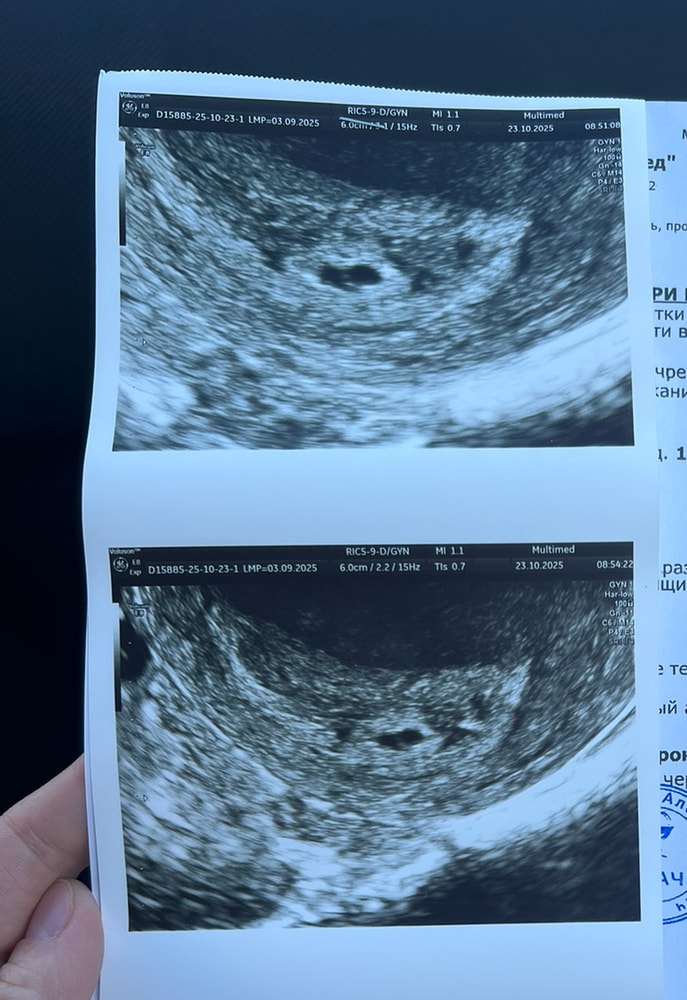

Сделала повторное узи спустя 6 дней. По прежнему замершая под вопросом.

В этот раз плодное яйцо уже похоже на плодное яйцо, но в нем нашли перегородку.

сказали, что вероятнее замершая, но стоит переделать опять узи через 5 дней🙈